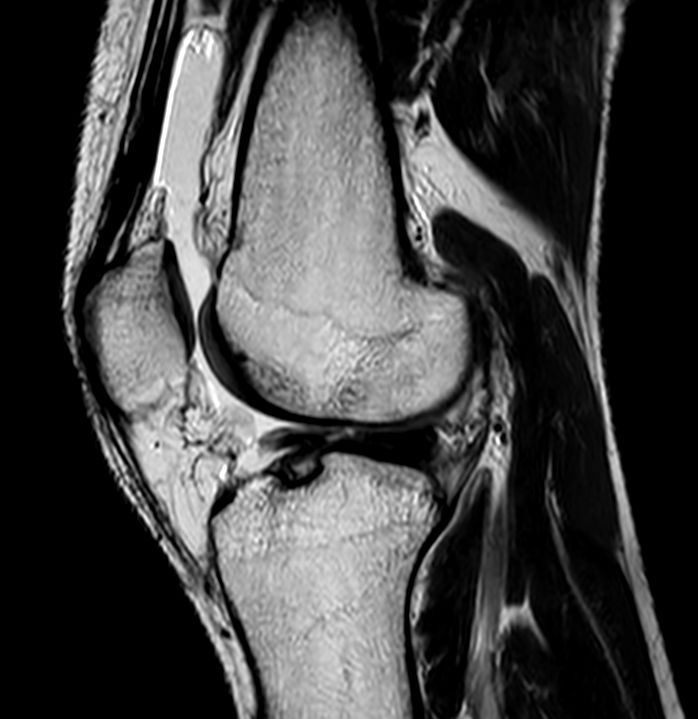

Sagittal 3D PDw TSE FatSat